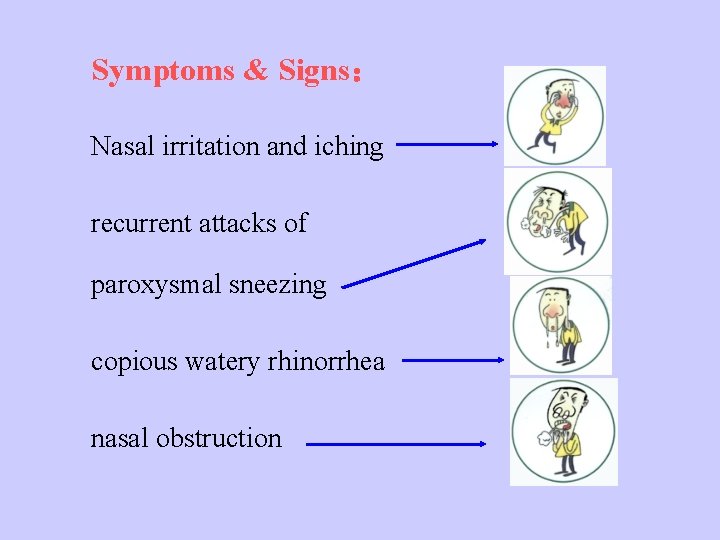

Symptoms & Signs: Nasal irritation and iching recurrent attacks of paroxysmal sneezing copious watery rhinorrhea nasal obstruction